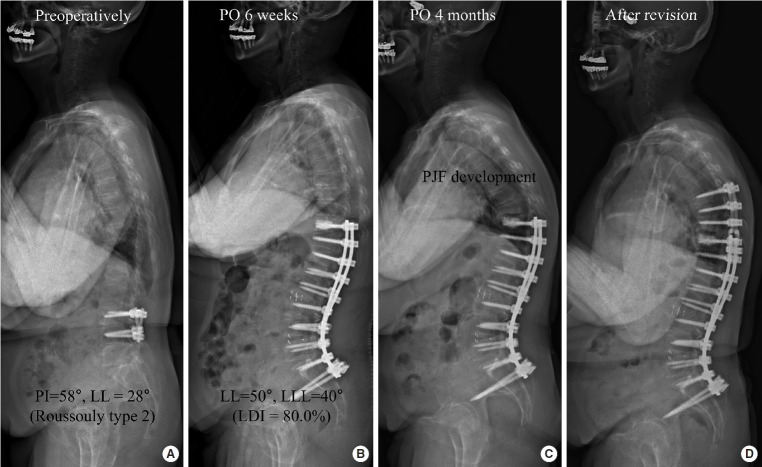

目的:探讨成人脊柱畸形(ASD)手术后近端关节功能衰竭(PJF)的危险因素。方法:该研究纳入了接受低胸骨盆融合治疗ASD的患者,并根据年龄调整的骨盆发生率减去腰椎前凸获得了理想的矫正。PJF在影像学上被定义为近端结膜角(PJA)为>28°,加上PJA的差异为>22°,或在临床上被定义为近端结膜并发症的翻修手术。评估临床和影像学变量以确定PJF的危险因素。结果:最终研究队列包括196例患者,其中女性170例(86.7%),平均年龄68.3岁。在平均45.9个月的随访期间,43例(21.9%)患者发生PJF。多因素logistic回归分析显示,老年人(优势比[OR], 1.063;95%置信区间[CI], 1.001-1.129;p=0.046),术前矢状纵轴大(OR, 1.007;95% ci, 1.001-1.013;p=0.024),不使用横突(TP)钩(OR, 5.556;95% ci, 1.205-19.621;p=0.028),高腰分布指数(LDI) (OR, 1.136;95% ci, 1.109-1.164;结论:相当大比例的患者(21.9%)尽管获得了理想的矢状面矫正,但仍发生了PJF。在避免过度LDI的情况下使用TP钩可以帮助进一步降低该患者组发生PJF的风险。

Methods: The study included patients who underwent low thoracic to pelvic fusion for ASD and obtained ideal correction according to age-adjusted pelvic incidence minus lumbar lordosis. PJF was defined either radiographically as a proximal junctional angle (PJA) of >28° plus a difference in PJA of >22° or clinically as revision surgery for proximal junctional complications. Clinical and radiographic variables were assessed to identify the risk factors for PJF.

Results: The final study cohort consisted of 196 patients, of whom 170 were women (86.7%), with an average age of 68.3 years. During mean follow-up duration of 45.9 months, PJF occurred in 43 patients (21.9%). Multivariate logistic regression analysis revealed that old age (odds ratio [OR], 1.063; 95% confidence interval [CI], 1.001-1.129; p=0.046), large preoperative sagittal vertical axis (OR, 1.007; 95% CI, 1.001-1.013; p=0.024), nonuse of a transverse process (TP) hook (OR, 5.556; 95% CI, 1.205-19.621; p=0.028), and high lumbar distribution index (LDI) (OR, 1.136; 95% CI, 1.109-1.164; p<0.001) were significant risk factors for PJF development.

Conclusion: A sizeable proportion of patients (21.9%) developed PJF despite achieving ideal sagittal correction. Using TP hooks with avoiding excessive LDI can be helpful to further mitigate the risk of PJF development in this patient group.